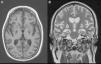

La TC y la RM (fig. 2) de control en el segundo mes de ingreso demuestran una destrucción casi completa de los ganglios basales debido a la electrocución y el daño anóxico. Un nuevo PET/TC realizado a los 6 meses del anterior confirma la destrucción de ganglios basales y la conservación del metabolismo de la corteza frontoparietal. Con el fin de controlar el estatus distónico, se implantaron 2 neuroestimuladores a nivel de ambos tálamos cerebrales que, aunque mejoraron parcialmente la clínica del paciente, tampoco controlaron las crisis totalmente. Una bomba intratecal de morfina permitió descender la dosis de las perfusiones de cisatracurio y benzodiacepinas de forma progresiva hasta su retirada, manteniendo en la actualidad solamente una dosis de 5mg de diazepam cada 8h vía enteral. El estatus distónico es de pésimo pronóstico, ya que todos los estudios de imagen demuestran un catastrófico daño estructural con desaparición casi completa de los ganglios de la base, pero en la actualidad, con los electroestimuladores, la bomba de morfina, las infiltraciones periódicas de toxina botulínica, la rehabilitación y el tratamiento farmacológico con diazepam y baclofeno, sus distonías se controlan aceptablemente.